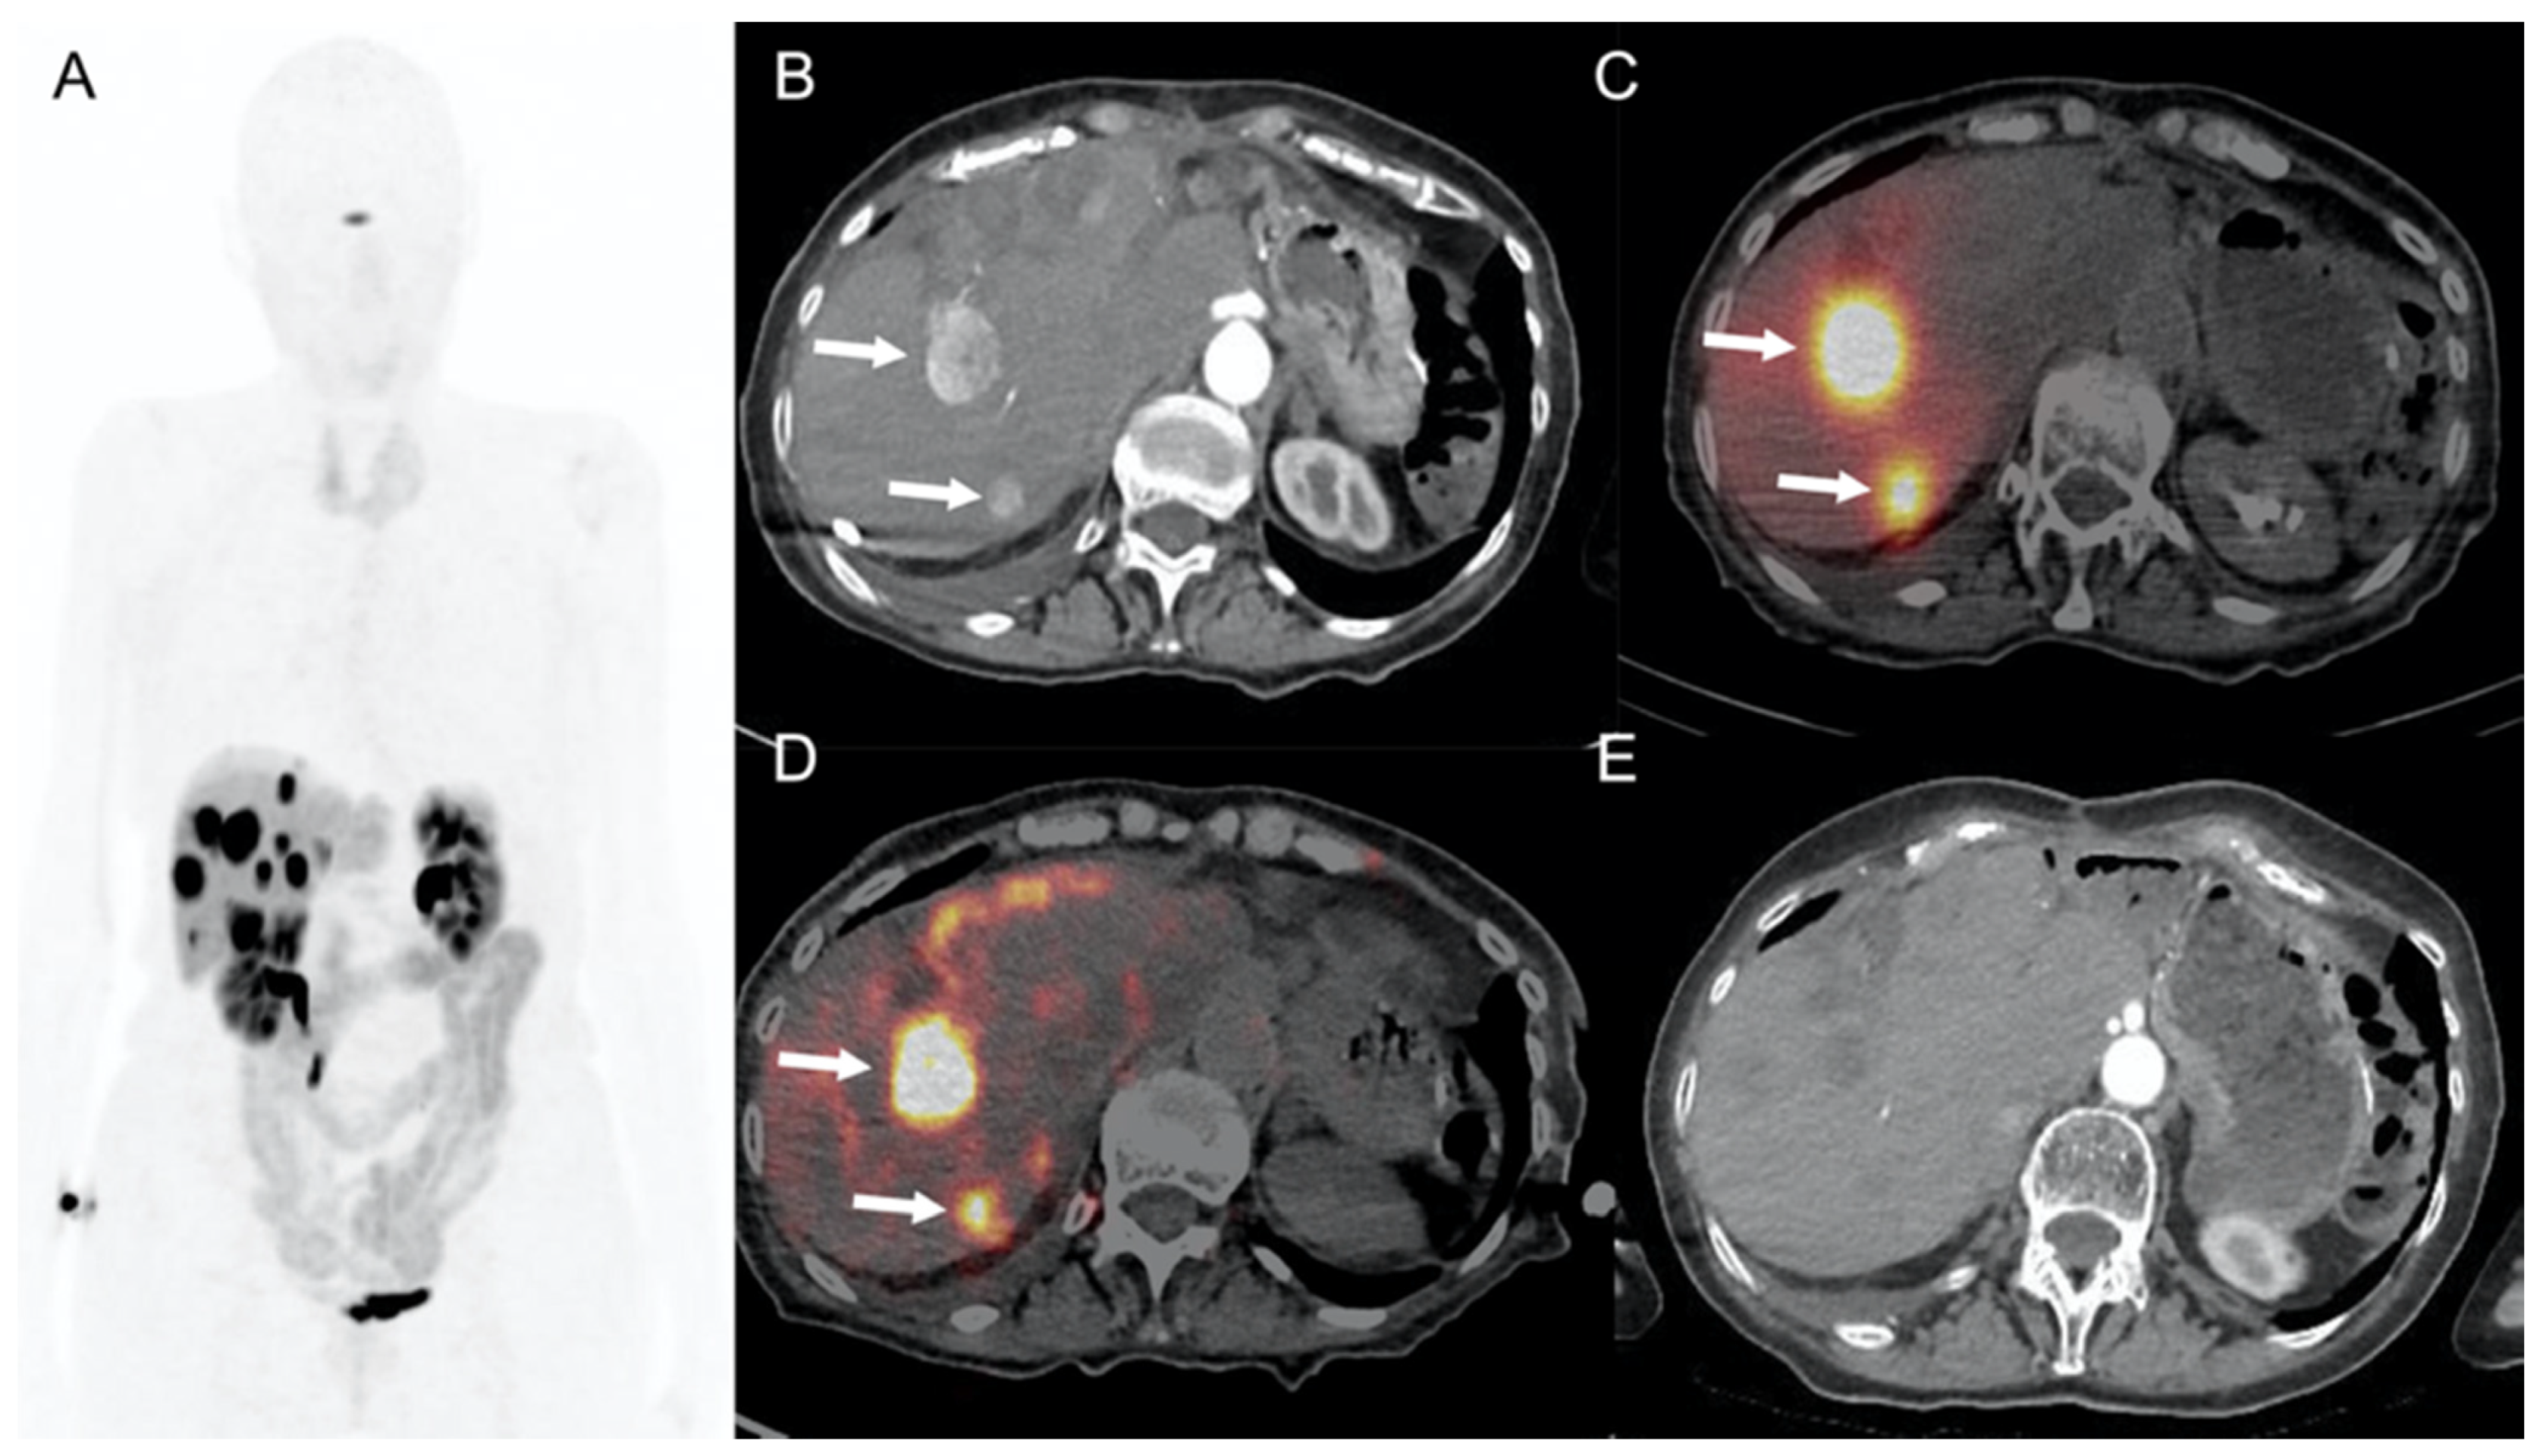

- Braat, A.J.A.T.; Ahmadzadehfar, H.; Kappadath, S.C.; Stothers, C.; Frilling, A.; Deroose, C.M.; Flamen, P.; Brown, D.B.; Sze, D.Y.; Mahvash, A.; et al. Radioembolization with 90Y Resin Microspheres of Neuroendocrine Liver Metastases After Initial Peptide Receptor Radionuclide Therapy. Cardiovasc. Interv. Radiol. 2020, 43, 246–253. [Google Scholar] [CrossRef] [PubMed] [Green Version]

- Strosberg, J.; El-Haddad, G.; Wolin, E.; Hendifar, A.; Yao, J.; Chasen, B.; Mittra, E.; Kunz, P.L.; Kulke, M.H.; Jacene, H.; et al. Phase 3 Trial of 177Lu-Dotatate for Midgut Neuroendocrine Tumors. N. Engl. J. Med. 2017, 376, 125–135. [Google Scholar] [CrossRef] [PubMed]

- Strosberg, J.; Wolin, E.; Chasen, B.; Kulke, M.; Bushnell, D.; Caplin, M.; Baum, R.P.; Kunz, P.; Hobday, T.; Hendifar, A.; et al. Health-Related Quality of Life in Patients with Progressive Midgut Neuroendocrine Tumors Treated with 177Lu-Dotatate in the Phase III NETTER-1 Trial. J. Clin. Oncol. 2018, 36, 2578–2584. [Google Scholar] [CrossRef] [PubMed]

- Kratochwil, C.; López-Benítez, R.; Mier, W.; Haufe, S.; Isermann, B.; Kauczor, H.-U.; Choyke, P.L.; Haberkorn, U.; Giesel, F.L. Hepatic arterial infusion enhances DOTATOC radiopeptide therapy in patients with neuroendocrine liver metastases. Endocr. Relat. Cancer 2011, 18, 595–602. [Google Scholar] [CrossRef] [Green Version]